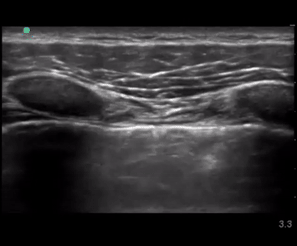

PneumoLens

Best in class lung sliding AI model currently undergoing regulatory validation.

This study examined the real-time diagnostic accuracy of artificial intelligence-assisted lung ultrasound (AI-LUS) in identifying absent lung sliding, crucial for pneumothorax diagnosis. Results indicated high sensitivity and moderate specificity for AI-LUS, suggesting its potential utility in clinical settings.

This study introduced a deep learning-based solution to automate the assessment of pneumothorax through lung ultrasound (LUS) by detecting lung sliding artifacts. Using data from two academic hospitals, researchers trained a binary classifier on M-mode (motion-mode) images extracted from B-mode (brightness-mode) videos.